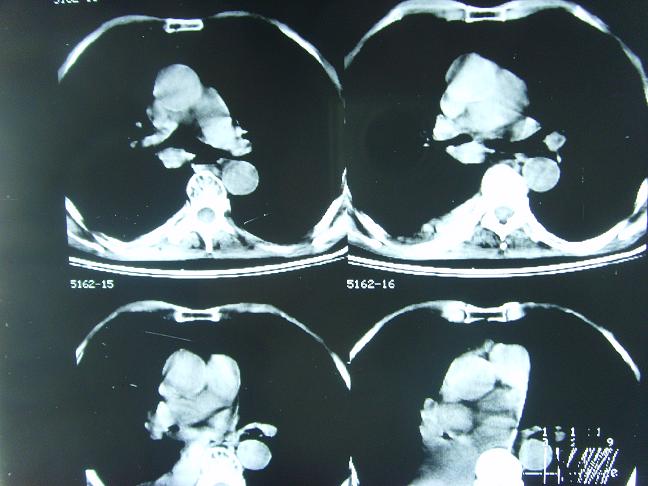

考虑  右肺新生物伴右下肺阻塞性肺炎,肺不张.右侧胸腔积液

考虑:右侧中心型肺癌伴下肺肺不张。

用数码相机要用黑白的档,支持右下肺阻塞性肺炎,肺不张.右侧胸腔积液,建议增强。

1)右肺中央型肺癌伴右肺下叶肺不张。2)慢性支气管炎,肺气肿。3)右侧胸腔积液。

1)右肺中央型肺癌伴右肺下叶肺不张。2)慢性支气管炎,肺气肿。3)右侧胸腔积液

右肺中央型肺癌伴右肺下叶肺不张。慢支肺气肿。右侧胸腔积液。